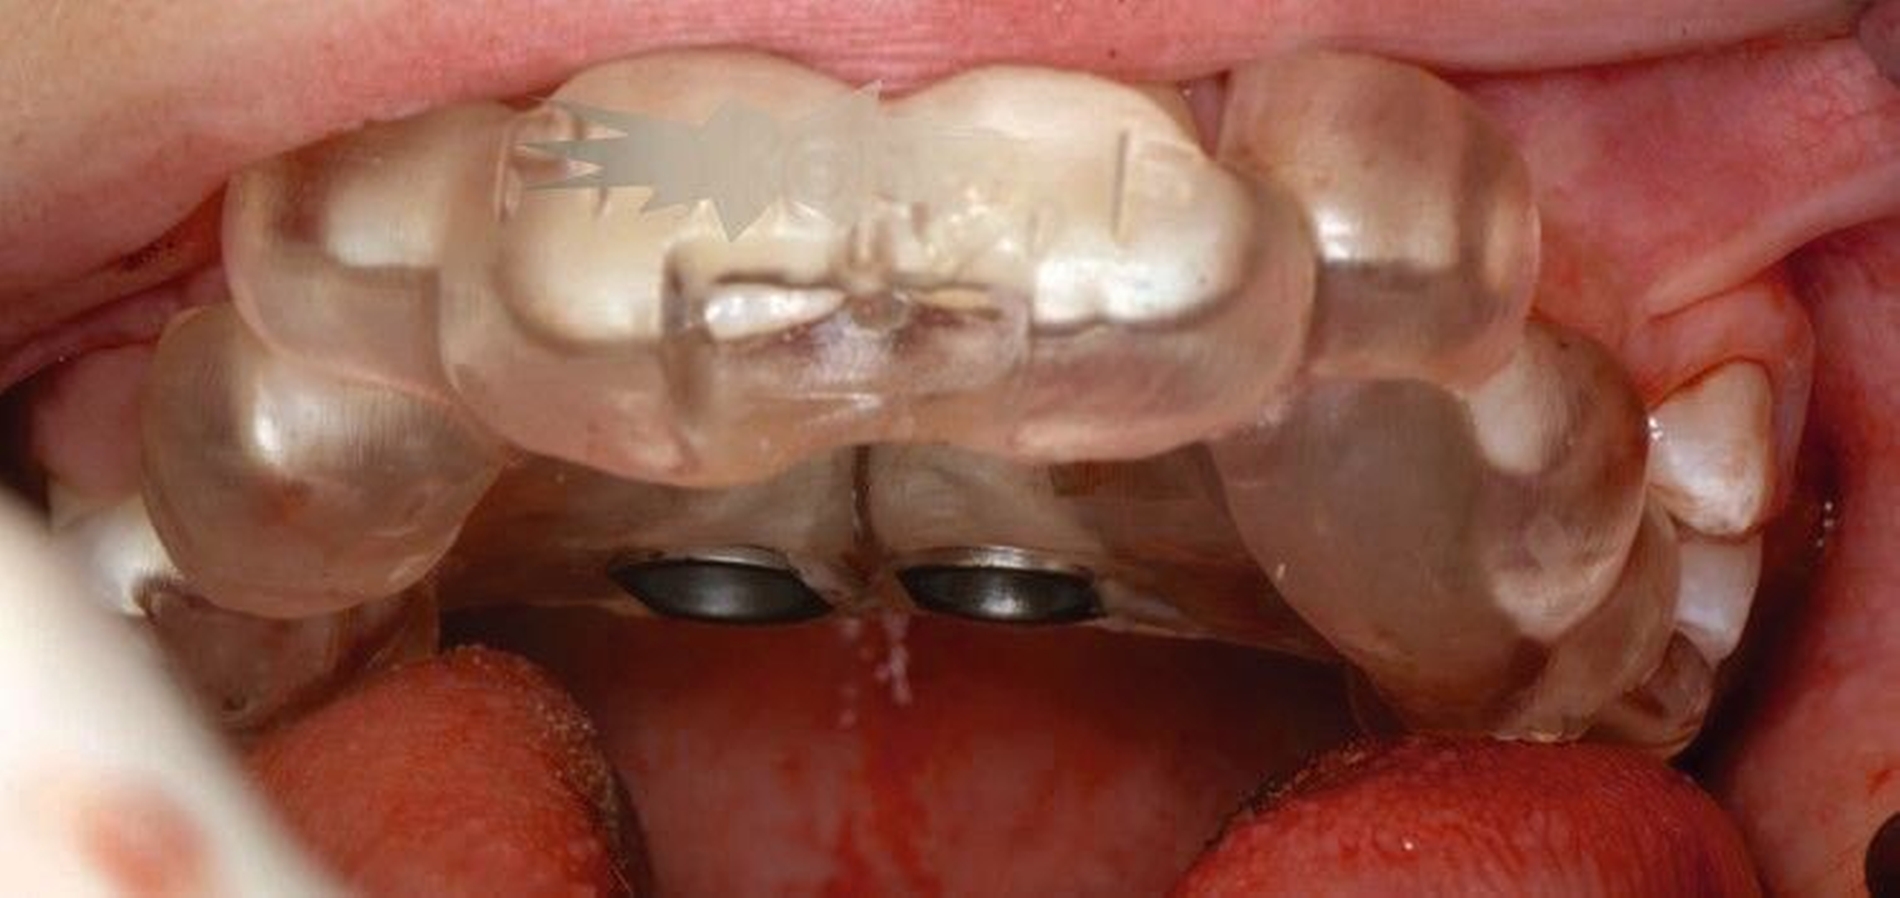

Die Zähne 36, 37, 46 und 47 wurden in Allgemeinanästhesie chirurgisch freigelegt. Zusätzlich wurden die beiden paramedianen Mini-Implantate (2 x 9 mm, Benefit System; PSM North America, Indio, CA) ohne Vorbohren mithilfe der zuvor hergestellten Schablone inseriert (Abbildung 3). Für die Platzierung der Mini-Implantate wurde ein Winkelschraubendreher verwendet. Direkt nach der Operation wurde die bmx DIRECT Hyrax-Schraube (10 mm, BENEfit®-System, Dentalline, Birkenfeld, Deutschland) an den Mini-Implantaten befestigt, um ein MARPE zu erzielen (Abbildung 4).